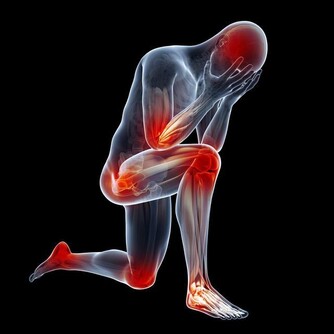

3.血栓45-55歲很容易出現血栓、腦血栓、肺栓塞、心梗等,

抽煙、高血壓、糖尿病、高血脂、久坐不動等都是患血栓的高危因素。

就像水管的水流速度慢,雜質容易沉積一樣。

輕者出現肢體偏癱拄拐等,重者直接威脅生命。

常見症狀

血栓雖然不像癌症那樣症狀比較明顯,但是依然會有一些異樣,

比如,很多腿部靜脈血栓患者前期都會出現“腿疼”,腦血栓患者普遍反映會出現頭痛、偏頭痛等。